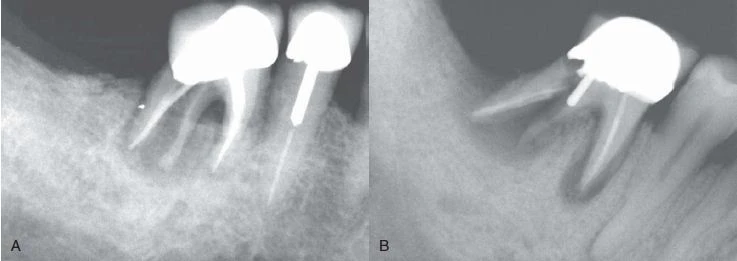

Hình 9. Đôi khi không có dấu hiệu rõ ràng cho thấy lý do răng có triệu chứng. (A) Hình ảnh X quang cho thấy răng cối lớn thứ hai hàm dưới có miếng trám sâu mức độ trung bình. (B) Thử tuỷ cho thấy răng chết tuỷ. Không chiếu sáng nên không thấy có đường nứt nào cả. (C) Chiếu ánh sáng có cường độ cao lên bề mặt răng, quan sát thấy vết nứt ở mặt ngoài. (D) Chiếu sáng vào mặt xa – trong của răng.